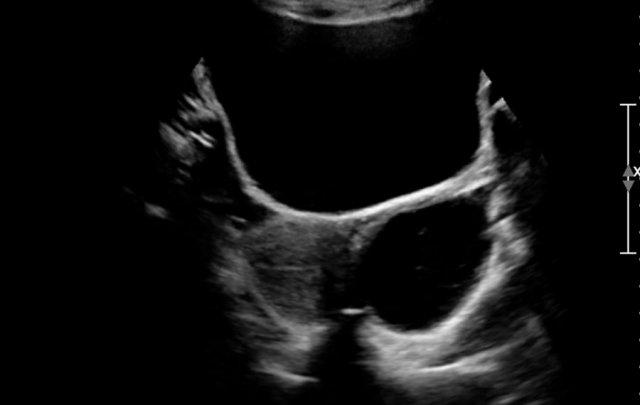

Đây là hình ảnh một nang được phát hiện trước sinh, được xác nhận sau khi sinh ở một bé gái sơ sinh.

Quan sát thấy một nang có mức dịch-dịch (fluid-fluid level).

Trong phẫu thuật, phát hiện xoắn buồng trứng trái.